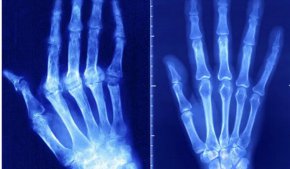

Автоимунните заболявания варират от диабет тип 1 до ревматоиден артрит, възпалително заболяване на червата и множествена склероза. Във всеки случай имунната система се пресича и включва здрави тъкани вместо инфекциозни агенти.